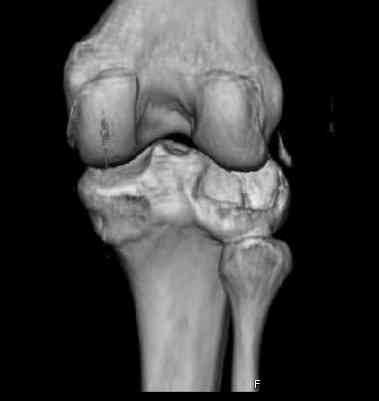

Здравствуйте, уважаемые коллеги!Подскажите, пожалуйста, какой выбрать доступ и способ фиксации при импрессионном переломе заднего отдела наружного мыщелка большеберцовой кости. Женщина 40 лет, травму получила 02.01.2008, катаясь на горных лыжах.Есть ли здесь необходимость использовать задний доступ, или можно справиться через наружный? Есть ли шансы сделать закрыто - под ЭОП через медиальное "окошко" поднять забойником суставную поврехность? Какой лучше использовать фиксатор?Спасибо.

Это техника применяется, когда имеется

центральная импрессия, а при ипрессии с краевым переломом - после приподнимания импрессии опорная (Butress) пластина, как на снимке.

In this situation, where the fragment is posterolateral, one needs a posterior approach, either as described by Timothy Bhatacharya et al in 2005 in JOT, which involves taking down the medial head of the gastrocnemius, or the Lobenhoffer paper which involves a transfibular approach.

would anyone consider an anterolateral approach with a sagital osteotomy just lateral to midline?

this would give access to the impacted posterior region. then "backgraft", and fix the osteotomy

fragment with a standard anterolateral plate. thanks.